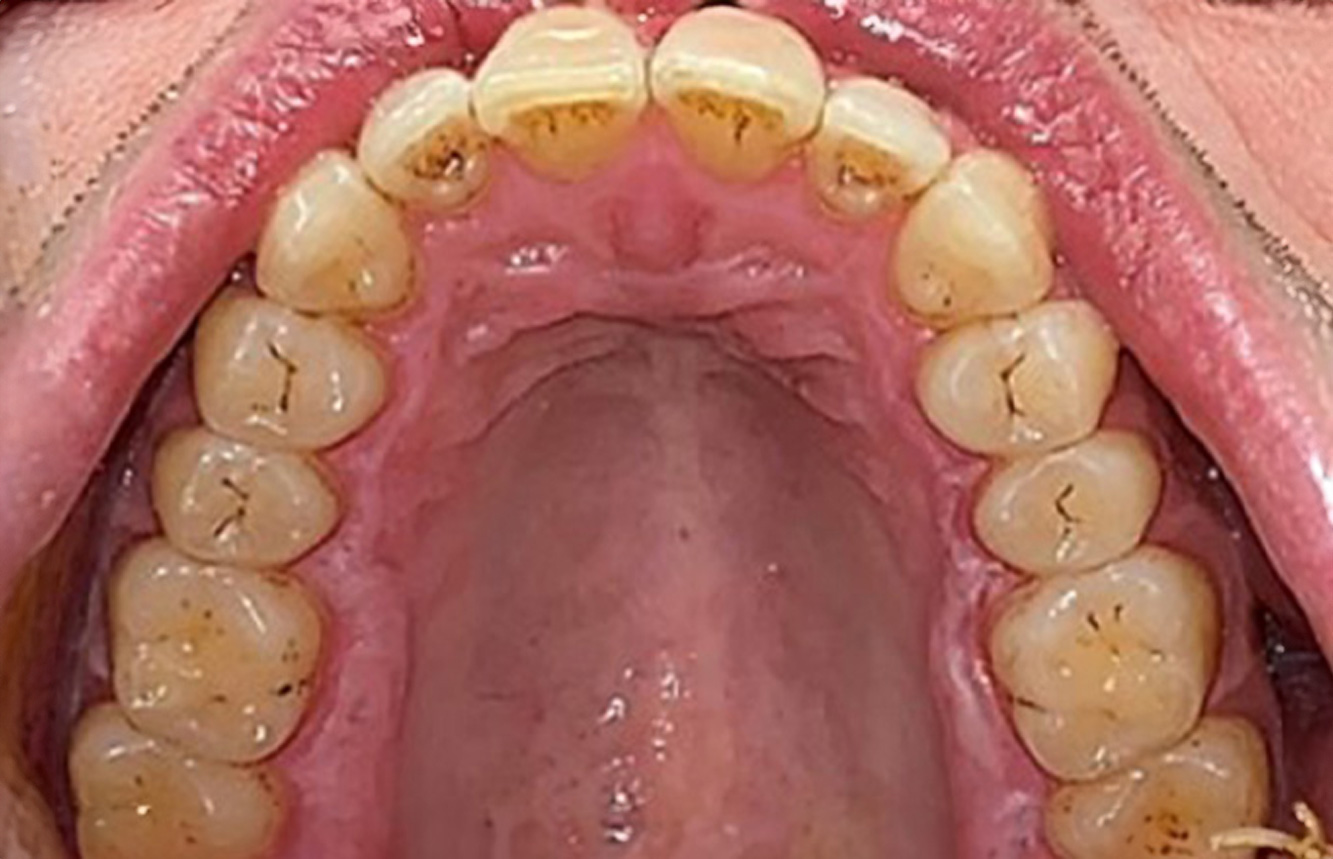

Următoarele studii de caz* acestea au rolul să ilustreze interacțiunea dintre necesitățile și factorii de risc definiți pentru IPC, precum și efectele factorilor individuali.

The healthy patient with pre-existing periodontal disease & peri-implantitis

A 52-year-old patient presents at a preventive care session. The patient has no systemic disease and is not taking any medication. He has had various dental treatments and also has two active carious lesions. In addition, the patient has four implants (2nd, 3rd and 4th quadrants). He is revealed to have early periodontal disease (stage IV, grade B). His periodontal condition is stable; a probing depth of Probing depths (ST) of 5 mm is only evident at the implant in region 36. Gingivitis is also identified. more